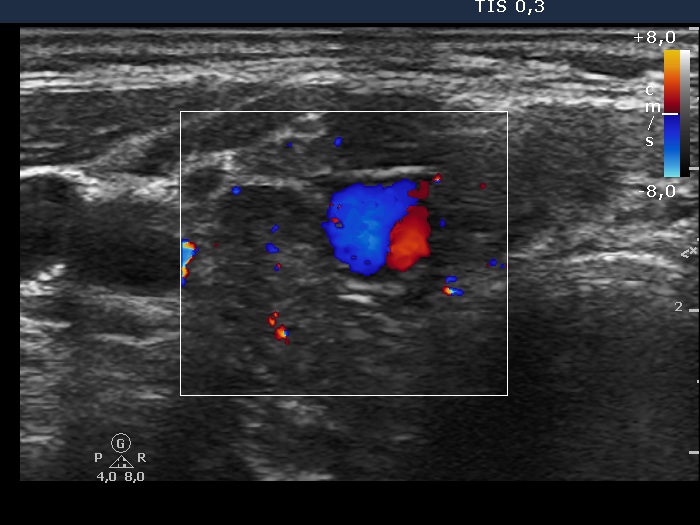

Ultrasonography: the thyroids were moderately hypoechogenic and contained numerous more hypoechogenic areas. These did not fit nodule. There was a relatively large vessel in the central part of the right lobe.